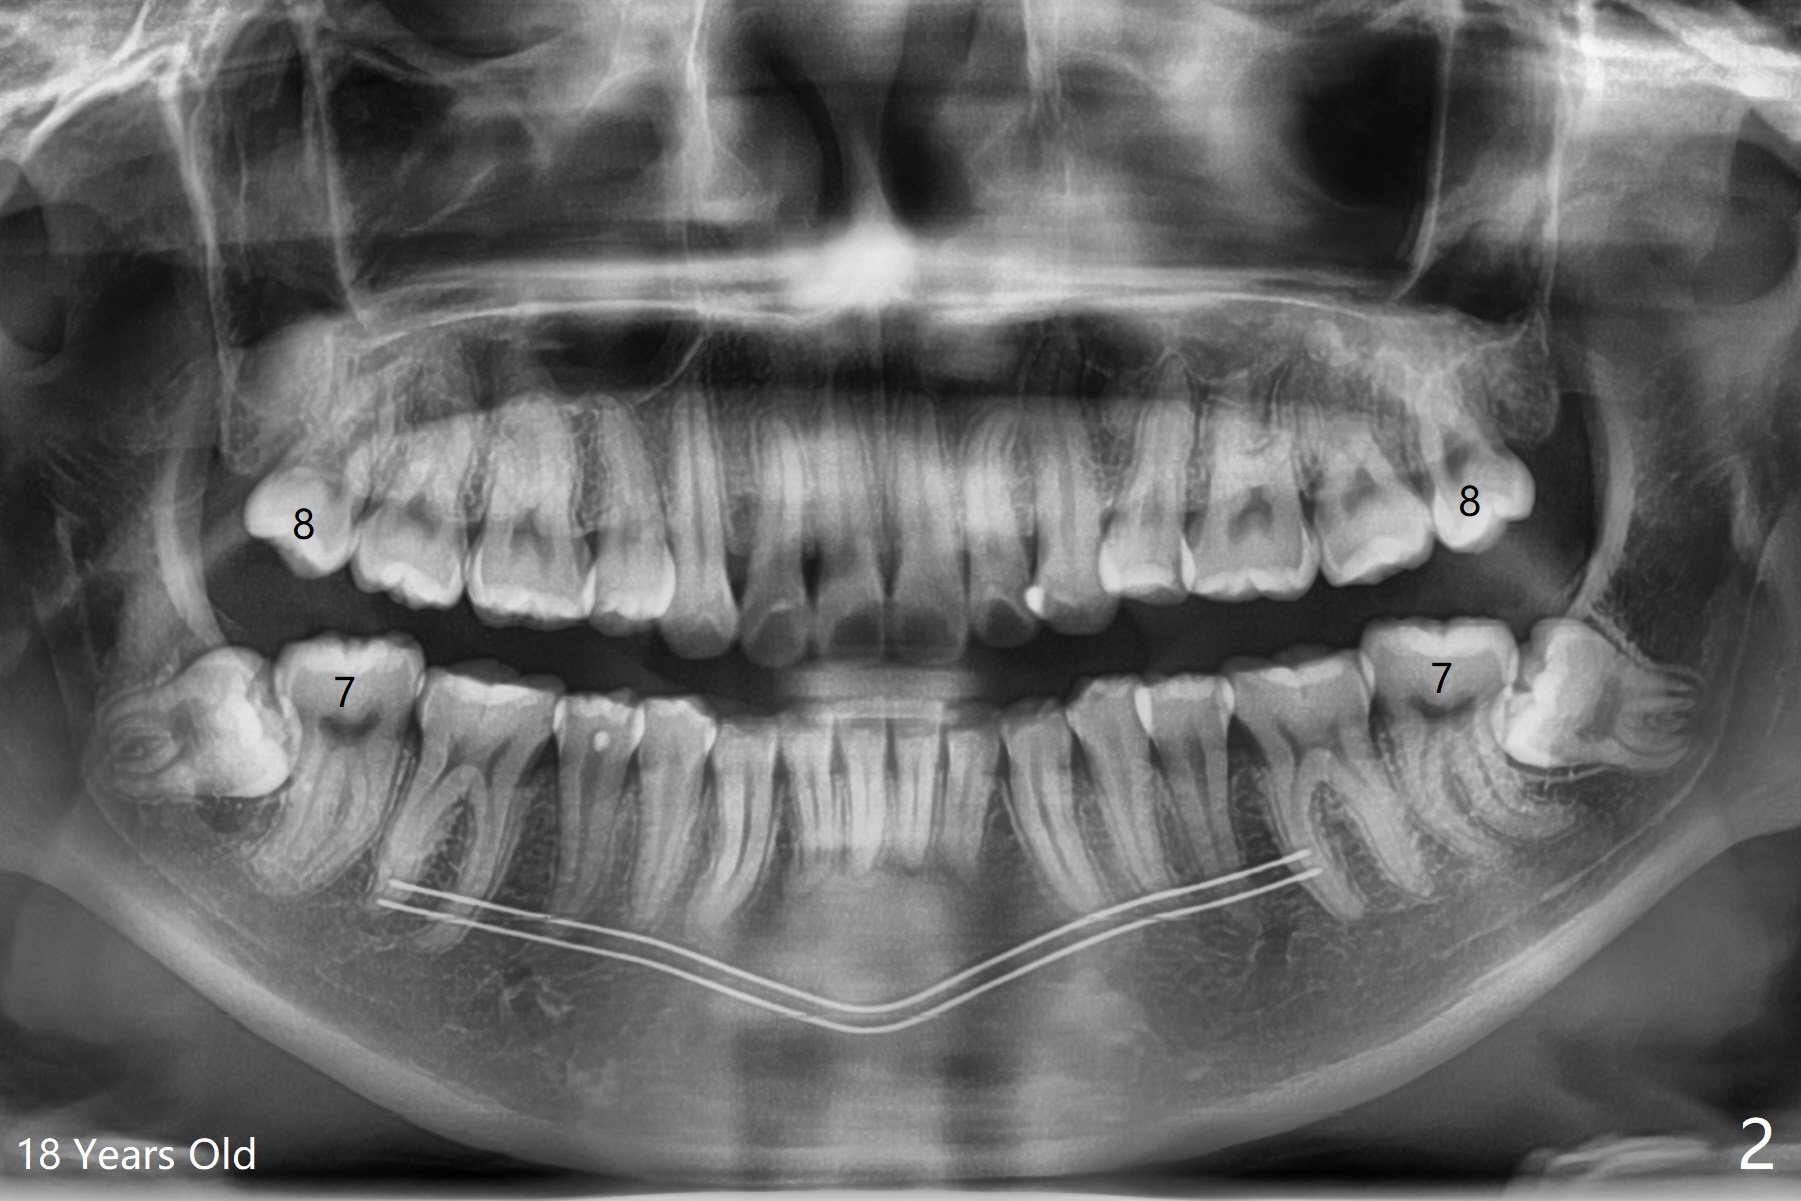

18岁女要求上大学前拔除智齿(图二),十三岁上四已经为了矫正而拔除(图一),所以现在只需要拔除下八,后者接近水平阻生,冠部可能位于下七远中颊侧(图三,四 *),所以附加切口应在七近中(红线)。智齿拔除后根部有两个牙槽窝(图五,六 *)。在右侧,塞入两个胶原塞(图七:1,2,collagen plug),其中一个末端剪开塞入根部牙槽窝。而左侧,使用一个胶原塞,但事先剪成两半(图八:1,3),第一部分也剪成燕尾,插入根部牙槽窝(1),然后在七远中放置骨水泥(1 cc Bond Apatite,2 红色),在后者上面放入胶原塞另外一半(3)。最后两侧都使用4-0 PGA 缝线。